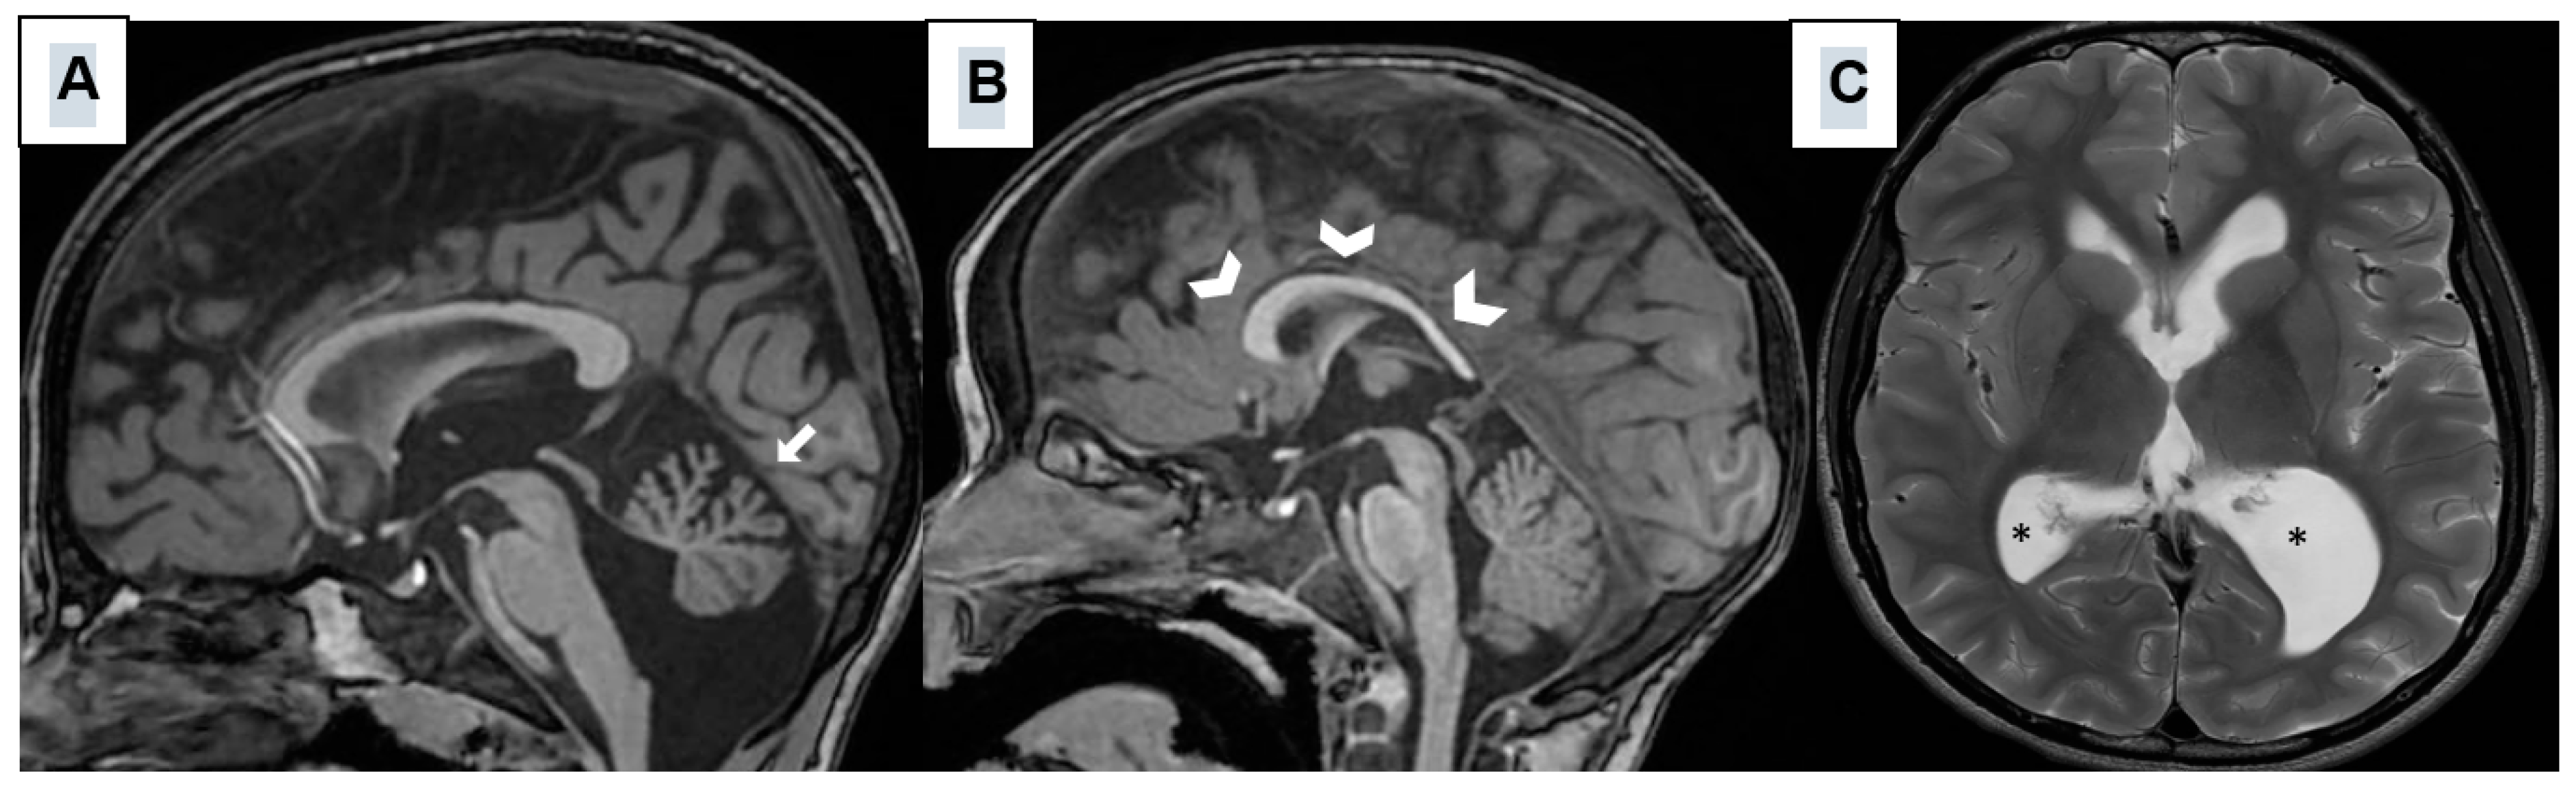

All the patients underwent brain MRI, which showed widespread malformations of the cerebellum, corpus callosum, and lateral ventricles. Figure 5 shows representative scans.

Figure 5.

Sagittal T1-weighted (A,B) and axial T2-weighted (C) MRI images obtained from three different SHMS patients and showing hypoplasia/atrophy of the cerebellar vermis (white arrow); (A), thin and dysmorphic corpus callosum (thick arrowhead) (B), enlarged and asymmetric lateral ventricles (*) (C).